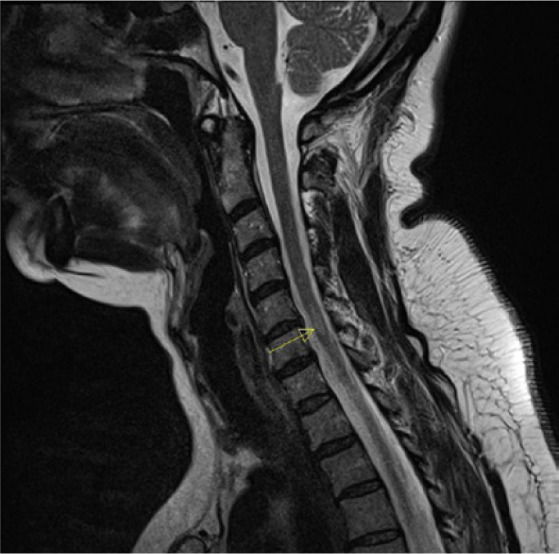

Case description: A 54-year-old female patient with quadriparesis, superficial sensory disturbance and gait and balance disorders was diagnosed with primary progressive MS according to McDonald's criteria. The magnetic resonance images were typical for MS. Previously, in 2013, she was diagnosed with SLE, treated successfully, and is currently in remission. After excluding neuropsychiatric lupus, ocrelizumab treatment was administered, with good clinical results.